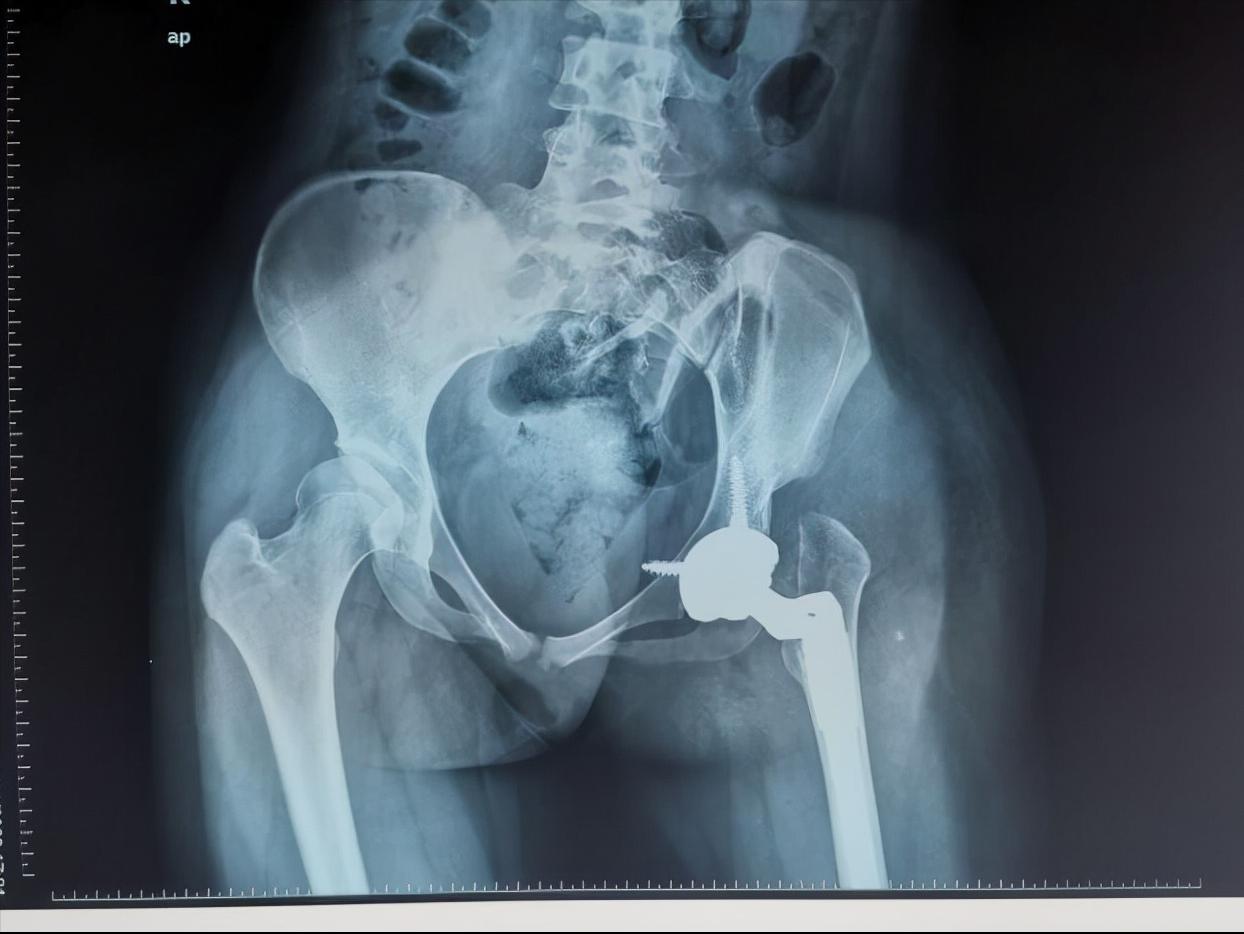

通过小张的的骨盆X线可以看到,她的左侧髋臼是一个发育不良的状态,髋臼较小较浅,外展角较大,而股骨头已经完全脱位,根据脱位高度分型为DDH(developmental dysplasia hip,发育性髋关节发育不良)IV型,已经属于最严重的程度了。

双下肢不等长

(骨盆正位片)